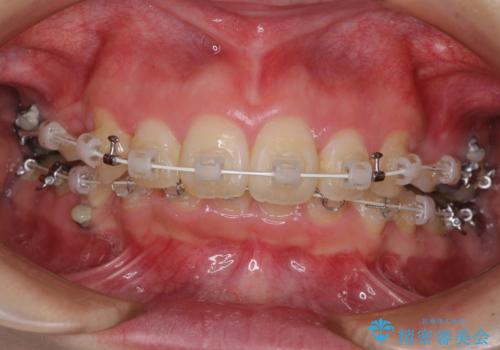

上顎前突を改善するために上顎左右第一小臼歯を抜歯し、補助装置を用いて上顎臼歯が前方に移動しないように工夫しながら、表側のワイヤー装置にて歯列を整えていくこととしました。

矯正治療後には、上顎欠損部をオールセラミックブリッジにて補綴治療を行うこととしました。